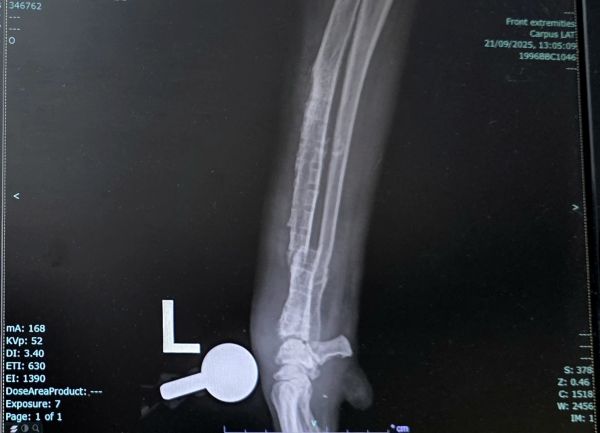

My 5-year-old Canaan dog (43 kg) had a distal radius-ulna fracture in his left front leg about three years ago, treated with a titanium plate and 12 locking screws. Since the surgery, he remained mildly lame but otherwise active and functioning well.

Recently, the lameness worsened - he began avoiding the leg completely. A CT scan indicated reasons to remove the implant, and a week and a half ago we went ahead with the removal surgery. He showed improvement over the next two days, but on day three, after suddenly jumping up in fear, he stopped using the leg again. An X-ray revealed a new fracture near the previous fixation site.

Attaching: CT before implant removal + Radiograph post-removal showing the new fracture.